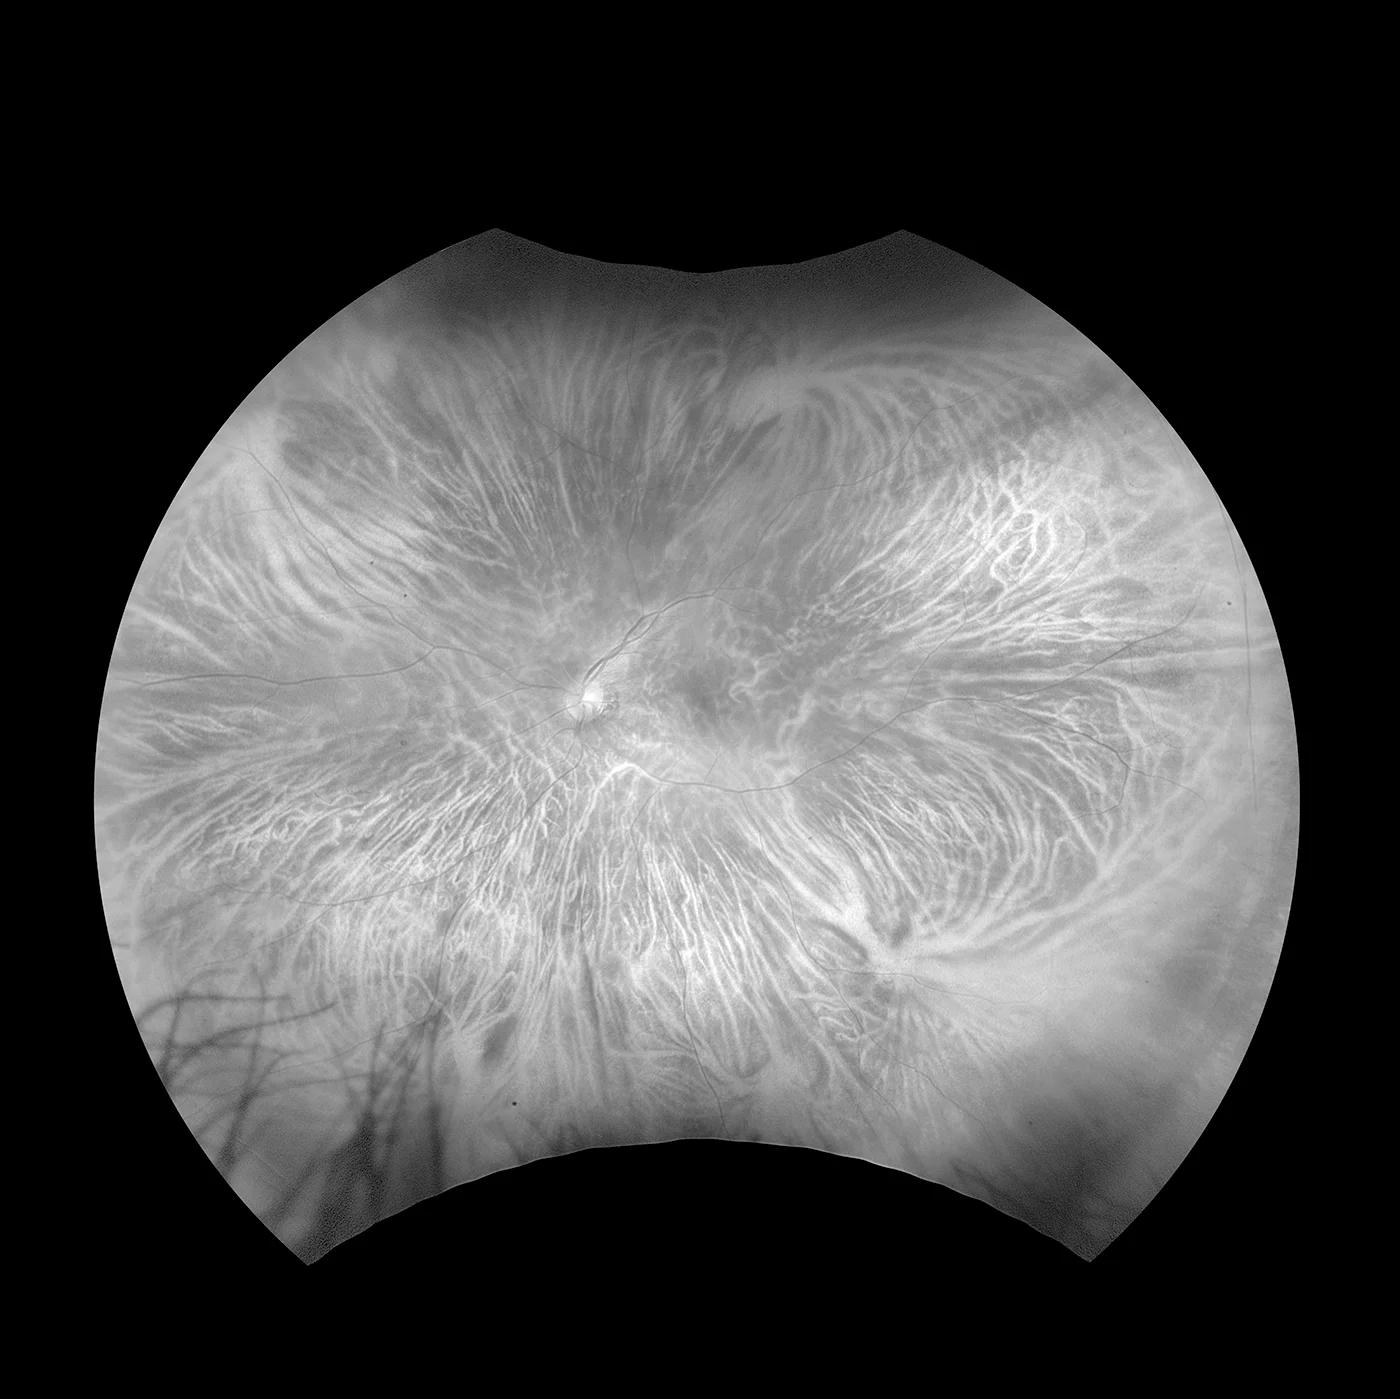

optomap Aderhaut

Im Gegensatz zu konventionellen Geräten, die mit weißem Licht arbeiten, scannen bei dieser Technologie zwei Laser-Wellenlängen mit niedriger Leistung gleichzeitig die Netzhaut. So können die retinalen Substrukturen in ihren jeweiligen Laserseparationen betrachtet werden. Die choroidal Darstellung umfasst den Scan vom RPE zur Aderhaut.